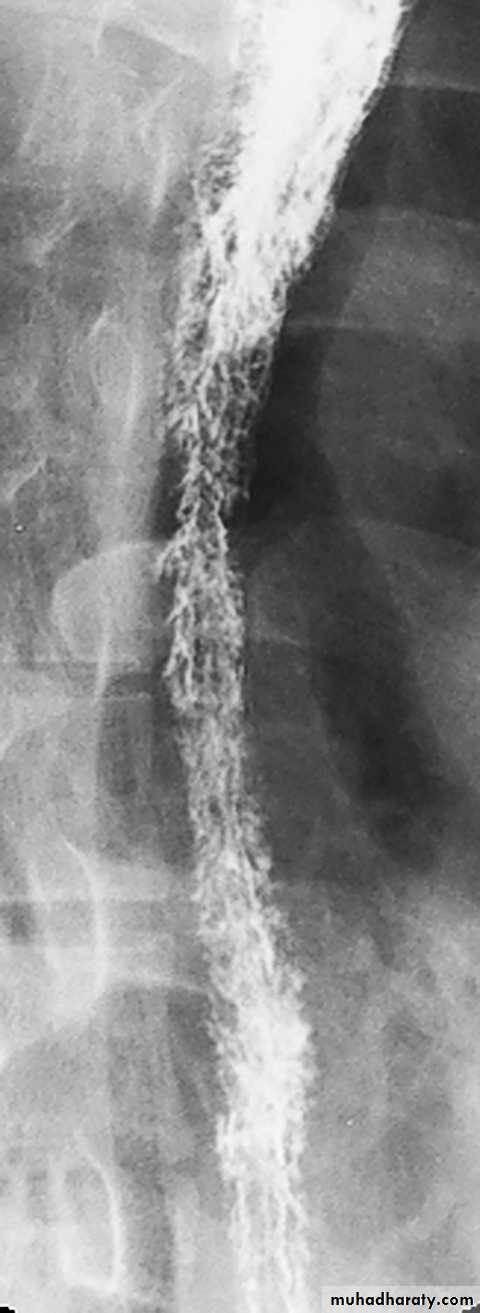

• Mucosal alteration

• Contour changes: physiological vs. pathological